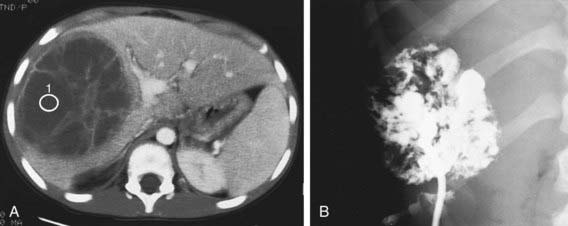

Figure 351-1 Liver abscess. A, Contrast-enhanced CT scan demonstrates a multioculated septated mass of decreased attenuation in the right lobe of the liver. There is increased attenuation of the septa. There is also faintly visible edema between the abscess and the enhanced normal liver. B, Injection of contrast material after percutaneous drainage of this documented streptococcal abscess demonstrates the multiocular nature of the lesion and its irregularly marginated wall.

(From Kuhn JP, Slovis TL, Haller JO: Caffrey’s pediatric diagnostic imaging, vol 2, ed 10, Philadelphia, 2004, Mosby, p 1470.)